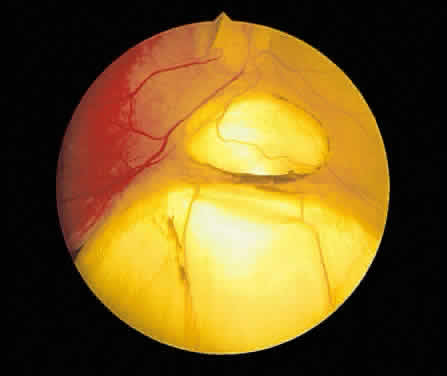

Degenerative or senile retinoschisis involves a splitting of the retina at the level of the outer plexiform layer for a distance of at least one disc diameter. As seen ophthalmoscopically, degenerative retinoschisis frequently has a “beaten metal” appearance, and fine, white dots may be seen within the cavity. These dots are thought to represent columns of Müller cells that have been stretched to the point of rupture: the clinically observed dots are Müller cell remnants that remain adherent to the internal limiting membrane. These Müller columns are believed to be responsible for the unevenness of the outer schisis surface; the inner surface is typically smooth. Large holes in the outer wall of the schisis cavity (by convention, “outer” refers to the scleral side of a retinal lesion whereas “inner” refers to the vitreous side of the retina) are frequently observed (Fig. 60), although smaller inner layer holes are less common. The presence of holes in both the inner and outer walls of a schisis cavity creates a pathway from the vitreous to the subretinal space, and a rhegmatogenous retinal detachment may develop.

Fig. 60. A. Photomicrograph of a retinoschisis cavity with a hole in the outer layer (OL). The inner layer (IL) is intact. Typical peripheral cystoid degeneration is present (arrow). B. Outer wall holes in a patient with senile retinoschisis. Notice the pocked marked appearance of the outer wall layer peripheral to the holes. (B, courtesy of William Benson, Philadelphia, PA, Wills Eye Atlas of Ophthalmology. Lippincott-Raven Fig 4-58, 1996)